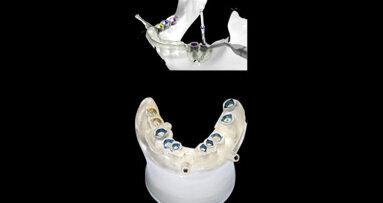

Nachdem die Osseointegration von Implantaten heute gut kalkulierbar ist und auch in kritischen, kompromittierten Situationen gelingt, wendet sich die Aufmerksamkeit nun der Langzeitstabilität des Weichgewebes zu. Das Wechselspiel zwischen marginaler Knochenreaktion und Weichgewebsposition stellt den Schlüssel zur Langzeitstabilität dar. Im anterioren Bereich wird die vertikale Position durch die spätere Position der Mukosa, also aus ästhetischen Gründen bestimmt. Dabei bieten Systeme mit stabiler Ankopplung und Platform Shift mittlerweile überzeugende Daten, sodass ein deutlich geringeres Remodeling auftritt, als die biologische Breite erwarten liesse. Unabhängig davon folgt die vertikale Positionierung im Seitenzahngebiet auch den Gegebenheiten der Höhe und des Platzangebotes der späteren Versorgung.